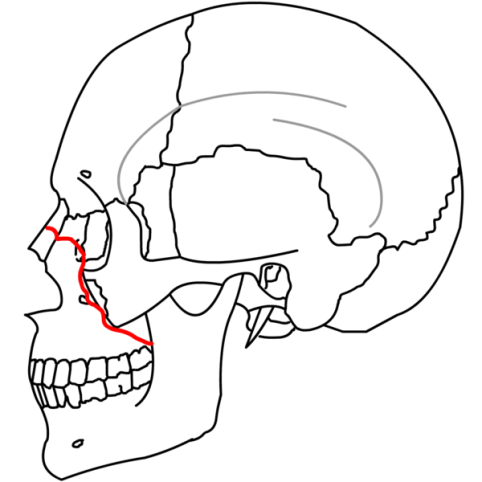

Mandible Fxs

| 1) Angle - Located distal to the 3rd Molar 2) Body - Usually extends from the region of the distal canine to 2nd / 3rd molar region 3) Parasymphysis - Involves fx anterior to the canines 4) Midline/Symphysis - fx located between the central incisors 5) Ramus - fx located superior to the angle 6) Condylar - Involves the condylar process superior to the ramus 7) Subcondylar - fx below/involving the sigmoid notch 8) Coronoid - Located in the area of the coronoid process superior to the ramus |